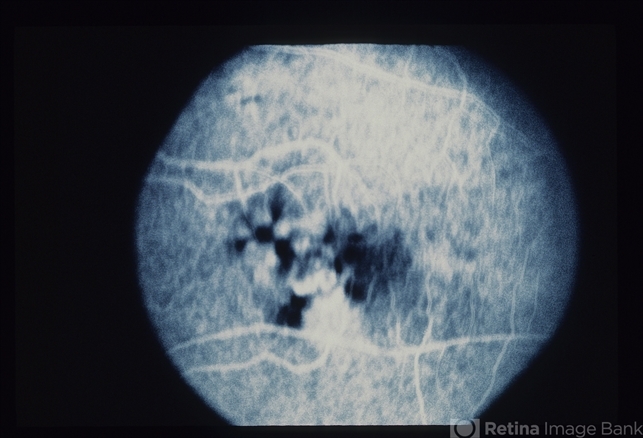

- ARMD SRNVM

- Condition/keywords

- subretinal neovascularization (SRNV)

- ARMD.